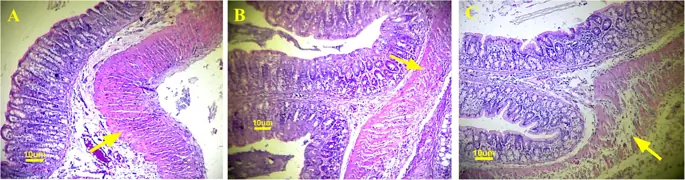

Гистопатологические данные показали больше неудач анастомоза в группе метамизола по сравнению с парацетамолом и контрольной группой ( рис. 1 ). Повреждение мышечных слоев, а также воспалительных тканей и грануляции, которые имели место в области анастомоза, оценивалось с использованием системы подсчета из гистологических образцов ( Рис. 2 ). Было обнаружено, что повреждение мышц в области анастомоза ободочной кишки было более тяжелым в группе метамизола (1, 57 ± 0, 8) по сравнению с парацетамолом (3 ± 1, 3) и контролем (3, 86 ± 0, 38) со значением р <0, 05. Парацетамол не имел негативных последствий повреждения мышц толстой кишки во время процесса анастомоза по сравнению с контролем (р> 0, 05).

Гистология толстой кишки анастомоза в каждой группе лечения (а. Контроль, б. Парацетамол, в. Метамизол). Структура серозного, подслизистого и слизистого слоев в области анастомоза разделена в группе метамизола, тогда как в парацетамоле и контрольной группе структура кишечной ткани лучше

Изображение в полном размере